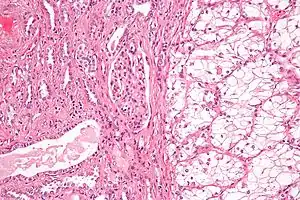

| Micrograph of the most common type of renal cell carcinoma (clear cell)—on right of the image; non-tumour kidney is on the left of the image. Nephrectomy specimen. H&E stain | |

Histopathology

The gross and microscopic appearance of renal cell carcinomas is highly variable. The renal cell carcinoma may present reddened areas where blood vessels have bled, and cysts containing watery fluids.[58] The body of the tumour shows large blood vessels that have walls composed of cancerous cells. Gross examination often shows a yellowish, multilobulated tumor in the renal cortex, which frequently contains zones of necrosis, haemorrhage and scarring. In a microscopic context, there are four major histologic subtypes of renal cell cancer: clear cell (conventional RCC, 75%), papillary (15%), chromophobic (5%), and collecting duct (2%). Sarcomatoid changes (morphology and patterns of IHC that mimic sarcoma, spindle cells) can be observed within any RCC subtype and are associated with more aggressive clinical course and worse prognosis. Under light microscopy, these tumour cells can exhibit papillae, tubules or nests, and are quite large, atypical, and polygonal.

The recommended histologic grading schema for RCC is the Fuhrman system (1982), which is an assessment based on the microscopic morphology of a neoplasm with haematoxylin and eosin (H&E staining). This system categorises renal cell carcinoma with grades 1, 2, 3, 4 based on nuclear characteristics. The details of the Fuhrman grading system for RCC are shown below:[62]